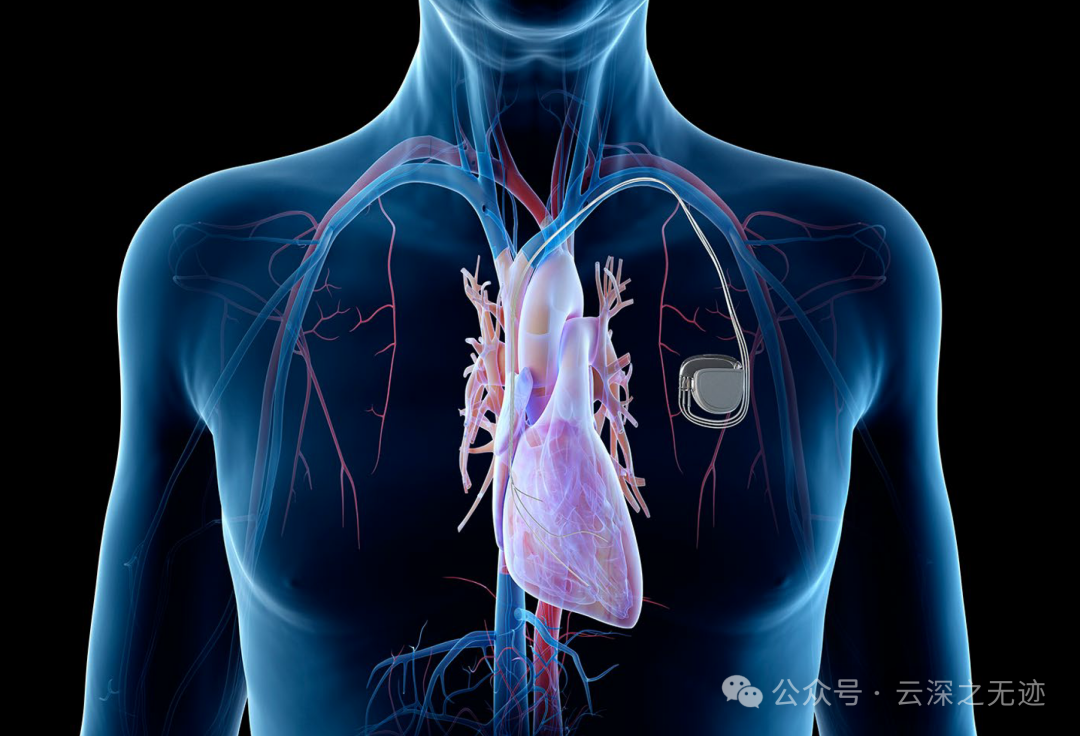

脉冲发生器定时发放一定频率的脉冲电流,通过导线和电极传输到电极所接触的心肌(心房或心室),使局部心肌细胞受到外来电刺激而产生兴奋,并通过细胞间的缝隙连接或闰盘连接向周围心肌传导,导致整个心房或心室兴奋并进而产生收缩活动。需要强调的是,心肌必须具备有兴奋、传导和收缩功能,心脏起搏方能发挥其作用。

这个图就很形象了